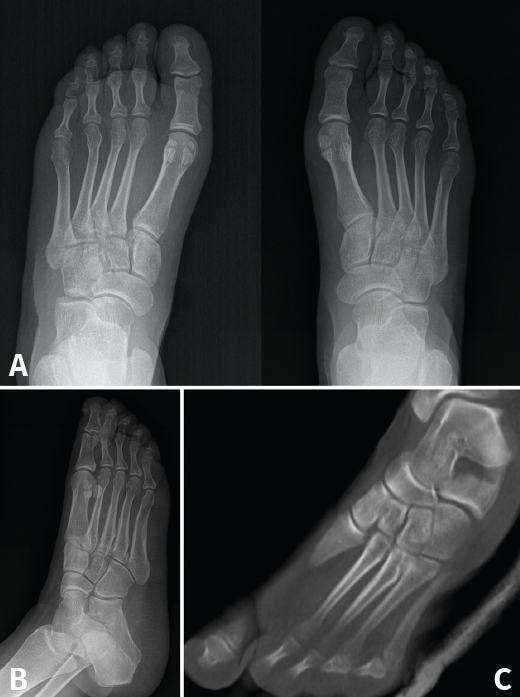

Se trata de una mujer de 26 años atendida en urgencias tras un traumatismo con torsión del pie. Se realiza radiografía y TAC, objetivando diástasis de 9 mm sin lesión ósea (Figura 3) y diagnosticando, por tanto, lesión sutil de Lisfranc.

Figura 3. Caso 2. A: radiografía preoperatoria anteroposterior con diástasis en la articulación de Lisfranc; B: radiografía oblicua preoperatoria; C: corte de tomografía computarizada oblicuo.